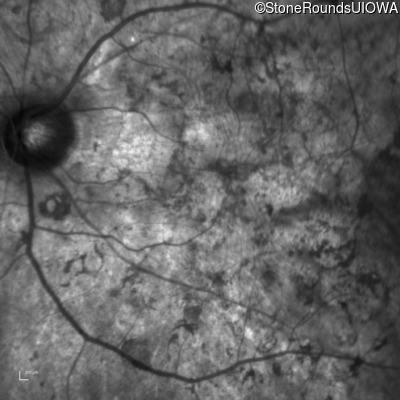

Infrared Fundus Photograph - Right - Hand Motion sc

Exemplar